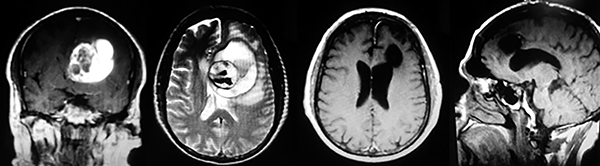

EJEMPLO DE CASO CLÍNICO (8)

Paciente femenino de 29 años de edad con historial de cefalea crónica que presenta súbitamente disdiadococinesia y dismetría izquierda.

El estudio de RMN presenta una lesión bien circunscrita en hemisferio cerebeloso izquierdo con periferia de predominio hiperintenso en T1 y T2, y centro hipointenso, edema perilesional mínimo, así como una imagen de un vaso venoso alimentador que recorre hacia el ángulo pontocerebeloso izquierdo.

Se realizó una craniectomía suboccipital paramedial derecha, así como un abordaje transcortical en el hemisferio cerebeloso izquierdo llegando a la región perilesional de aspecto amarillento, posteriormente se observa una lesión oscuro-verdoso de contenido hemático antiguo, retirando la cápsula y su contenido en la totalidad.

La evolución clínica de la paciente fue satisfactoria solo preservando la dismetría como secuela.

El resultado histopatológico fue consistente en angioma cavernoso.

El estudio de control de RMN se observa la brecha quirúrgica y ausencia de lesión (figs. 1, 2 y 3).

Figura 1:

Lesión cerebelosa izquierda ponderaciones en T1 y T2, la flecha señala vaso nutricio hacia el ángulo pontocerebeloso izquierdo, se puede observar el centro de intensidad heterogénea con contenido quístico multiloculado y edema perilesional leve.

Figura 2:

Cortes axiales en ponderación T1, cambios postquirúrgicos.

EJEMPLO DE CASO CLÍNICO (9)

Paciente masculino de 34 años de edad, quien presenta crisis convulsivas parciales motoras de brazo y hemicara derecha, secundariamente generalizadas, posteriormente hemiparesia 4/5 para hemicuerpo derecho.

La TAC muestra un área hiperdensa a nivel frontal izquierdo heterogénea que no refuerza con medio de contraste.

LA RMN muestra una lesión bien circunscrita frontal parasagital izquierda con edema perilesional, hiperintensa en T1 y T2, de contenido sólido y quístico, con poca captación del medio de contraste.

Se realizó craneotomía frontal para abordaje interhemisférico anterior.

Se realiza resección total de la lesión de contenido hemático oscuro-verdoso, consistente en un angioma cavernoso. La RMN postoperatoria se observa solo la brecha quirúrgica sin evidencia de lesión.

En el postquirúrgico el paciente desarrollo síndrome frontal lateral, que se controló con Risperidona y remitió después de tres semanas, las crisis convulsivas remitieron y el medicamento se disminuyó de manera paulatina (figs. 4 y 5).

Figura 4:

Imágenes prequirúrgicas y postquirúrgicas de lesión multiloculada del caso 9.